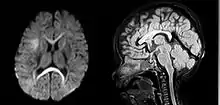

| An MRI of a patient with benign familial macrocephaly (male with head circumference > 60 cm) | |

Macrocephaly is a condition in which circumference of the human head is abnormally large.[1] It may be pathological or harmless, and can be a familial genetic characteristic. People diagnosed with macrocephaly will receive further medical tests to determine whether the syndrome is accompanied by particular disorders. Those with benign or familial macrocephaly are considered to have megalencephaly.